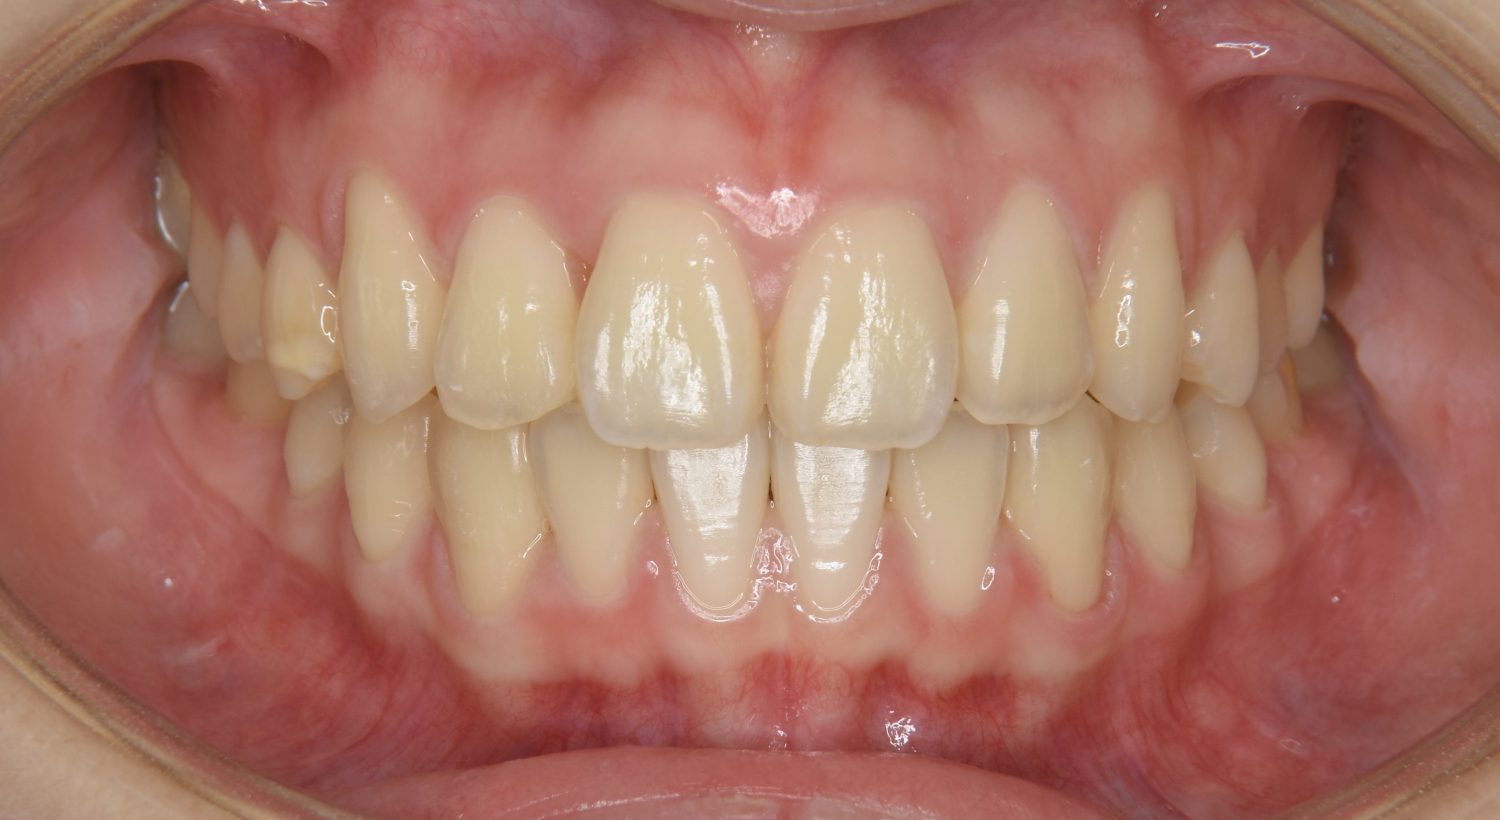

前歯部開咬の症例紹介②

Before

After

主訴

前歯で物が噛めない

治療内容

上下ラビアルブラケット(唇側装置)に矯正用アンカースクリューを併用し非抜歯で治療を行いました。

上下の前歯が開いており前歯では全く噛めていない状態でした。臼歯の圧下を行うことで機能面のみでなく審美面も改善しました。